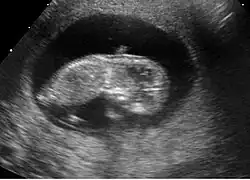

Fœtus à 12 semaines

Dans la plupart des cas, une échographie pratiquée à 12 semaines permet de détecter de nombreuses pathologies. Bien entendu, cette détection dépend de nombreux facteurs qui ne sont pas tous du ressort du médecin. Le surpoids et l'obésité sont actuellement les facteurs limitants les plus importants.

Figure 7. La distinction des organes intra-abdominaux est possible à 12 semaines

Sur la figure 7 on distingue à gauche une zone intra-abdominale blanche correspondant à l'intestin du fœtus. Dans cette zone blanche, une petite tache noire qui est la vessie. Enfin, à droite des intestins, on peut distinguer le foie et les poumons.

Les 2 bras d'un fœtus à 12 semaines

La face est explorable. Les deux orbites sont distinguables ainsi que les deux cristallins. Les membres se distinguent nettement. Le diagnostic d'anomalie des membres est possible à ce stade.

Les malformations graves du cerveau sont détectables comme l'anencéphalie ou l'holoprosencéphalie. Les malformations cardiaques ne sont pas détectables en routine à ce terme.